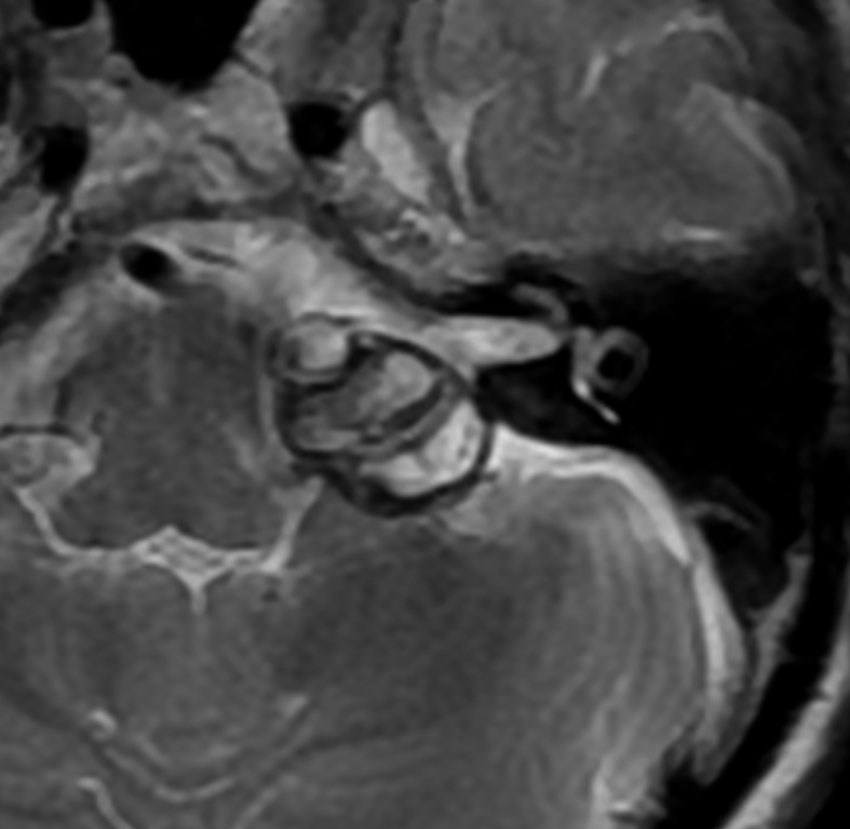

脳幹部の海綿状血管腫を手術するとき

左上のT2*でみられるように多発性海綿状血管腫の成人男性に発生した中脳海綿状血管腫です。複視と歩行失調で発症して,数回の脳幹部出血を繰り返し,水頭症になったために第3脳室開窓術がなされました。それでも出血は止まらず、両側の動眼神経麻痺による両側眼瞼下垂,歩行失調,嚥下障害などさまざまな中脳症状が進行しました。

しかたがないので手術で摘出しました。なんとか眼瞼が持ち上がるようになり歩行も可能で嚥下もできます。幸いだったのは感覚路(脊髄視床路)の障害による体性疼痛が生じなかったことです。

手術は経テント法 OTA という手法でした(クリックと手技が書いてあります)

片方の下丘の損傷だけでは神経脱落症状が出ないので,中脳内部の腫瘍を摘出するには下丘という狭い場所を切開して入りますが,この患者さんは左上丘も出血のために破壊されていて,間口が広かったといえます。でもこの手術は難しすぎるので決して積極的にはしません。